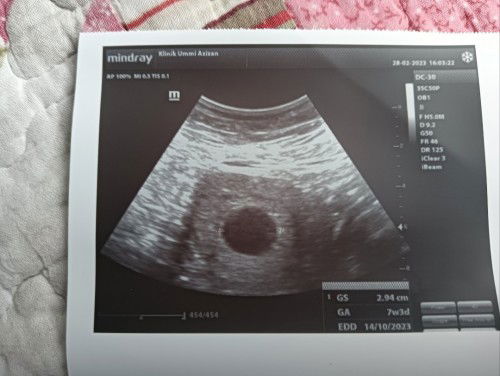

Hi ibu ibu semua... Hmm.... Tak tahu nk positive ke nk sedih.... Sepatut nya hari ni dah 9w4d... Saya repeat scan after 2weeks.. Kantung masih kosong... Takde baby... Saiz kantung 7w3d... Doc bagitaw , kalau 2 minggu lagi kosong juga... Kena cuci kat hospital... Emmm... Saya mmg takde alahan... Anak 1st pon mmg takde alahan... Ada kata kata yg boleh bg saya kuat tak... 🥺😔 #feelsad #thinkpositive #advicepls